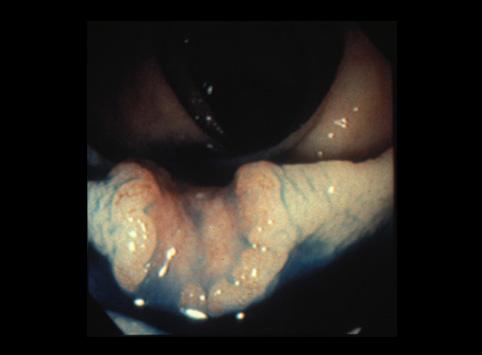

명확한 차이가 있는 중심함몰이 나타난 표면융기함몰형(IIa+IIc형) sm조기대장암

0형(표재형)/IIa형(IIa+IIc)

10~14

sm